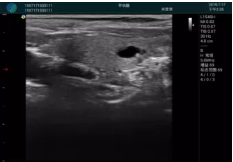

可視化甲狀腺穿刺引導(dǎo)

頸動(dòng)脈血流充盈飽滿,無外溢

肝內(nèi)血管顯示清晰,血流敏感無外溢

病例二:

甲狀腺囊性結(jié)節(jié),囊壁鈣化,透聲好

甲狀腺囊性占位

2001年美國(guó)健康護(hù)理研究和質(zhì)量監(jiān)督局(AHRQ)批準(zhǔn)了一項(xiàng)關(guān)于提高患者安全性的報(bào)告,建議:在頸內(nèi)靜脈中心置管術(shù)時(shí)使用超聲引導(dǎo)。此后超聲引導(dǎo)穿刺被用于幾乎所有的急診穿刺操作,尤其是血管穿刺。

便攜超聲在急診穿刺中的應(yīng)用:

* 提高了穿刺成功率

* 減少了穿刺損傷及并發(fā)癥

* 縮短了操作時(shí)間

* 減輕了患者痛苦